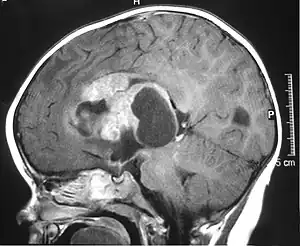

MRI of an AT/RT

The initial diagnosis of a tumor is made with a radiographic study (MRI[20] or CT-). If CT was performed first, an MRI is usually performed as the images are often more detailed and may reveal previously undetected metastatic tumors in other locations of the brain. In addition, an MRI of the spine is usually performed. The AT/RT tumor often spreads to the spine. AT/RT is difficult to diagnose only from radiographic study; usually, a pathologist must perform a cytological or genetic analysis.

The tumors' appearance on CT and MRI are not specific, tending towards large size, calcifications, necrosis (tissue death), and hemorrhage (bleeding). Radiological studies alone cannot identify AT/RT; a pathologist almost always has to evaluate a brain tissue sample.

The increased cellularity of the tumor may make the appearance on an uncontrasted CT to have increased attenuation. Solid parts of the tumor often enhance with contrast MRI finding on T1 and T2 weighted images are variable. Precontrast T2 weighted images may show an isosignal or slightly hypersignal. Solid components of the tumor may enhance with contrast, but not always. MRI studies appear to be more able to pick up metastatic foci in other intracranial locations, as well as intraspinal locations.